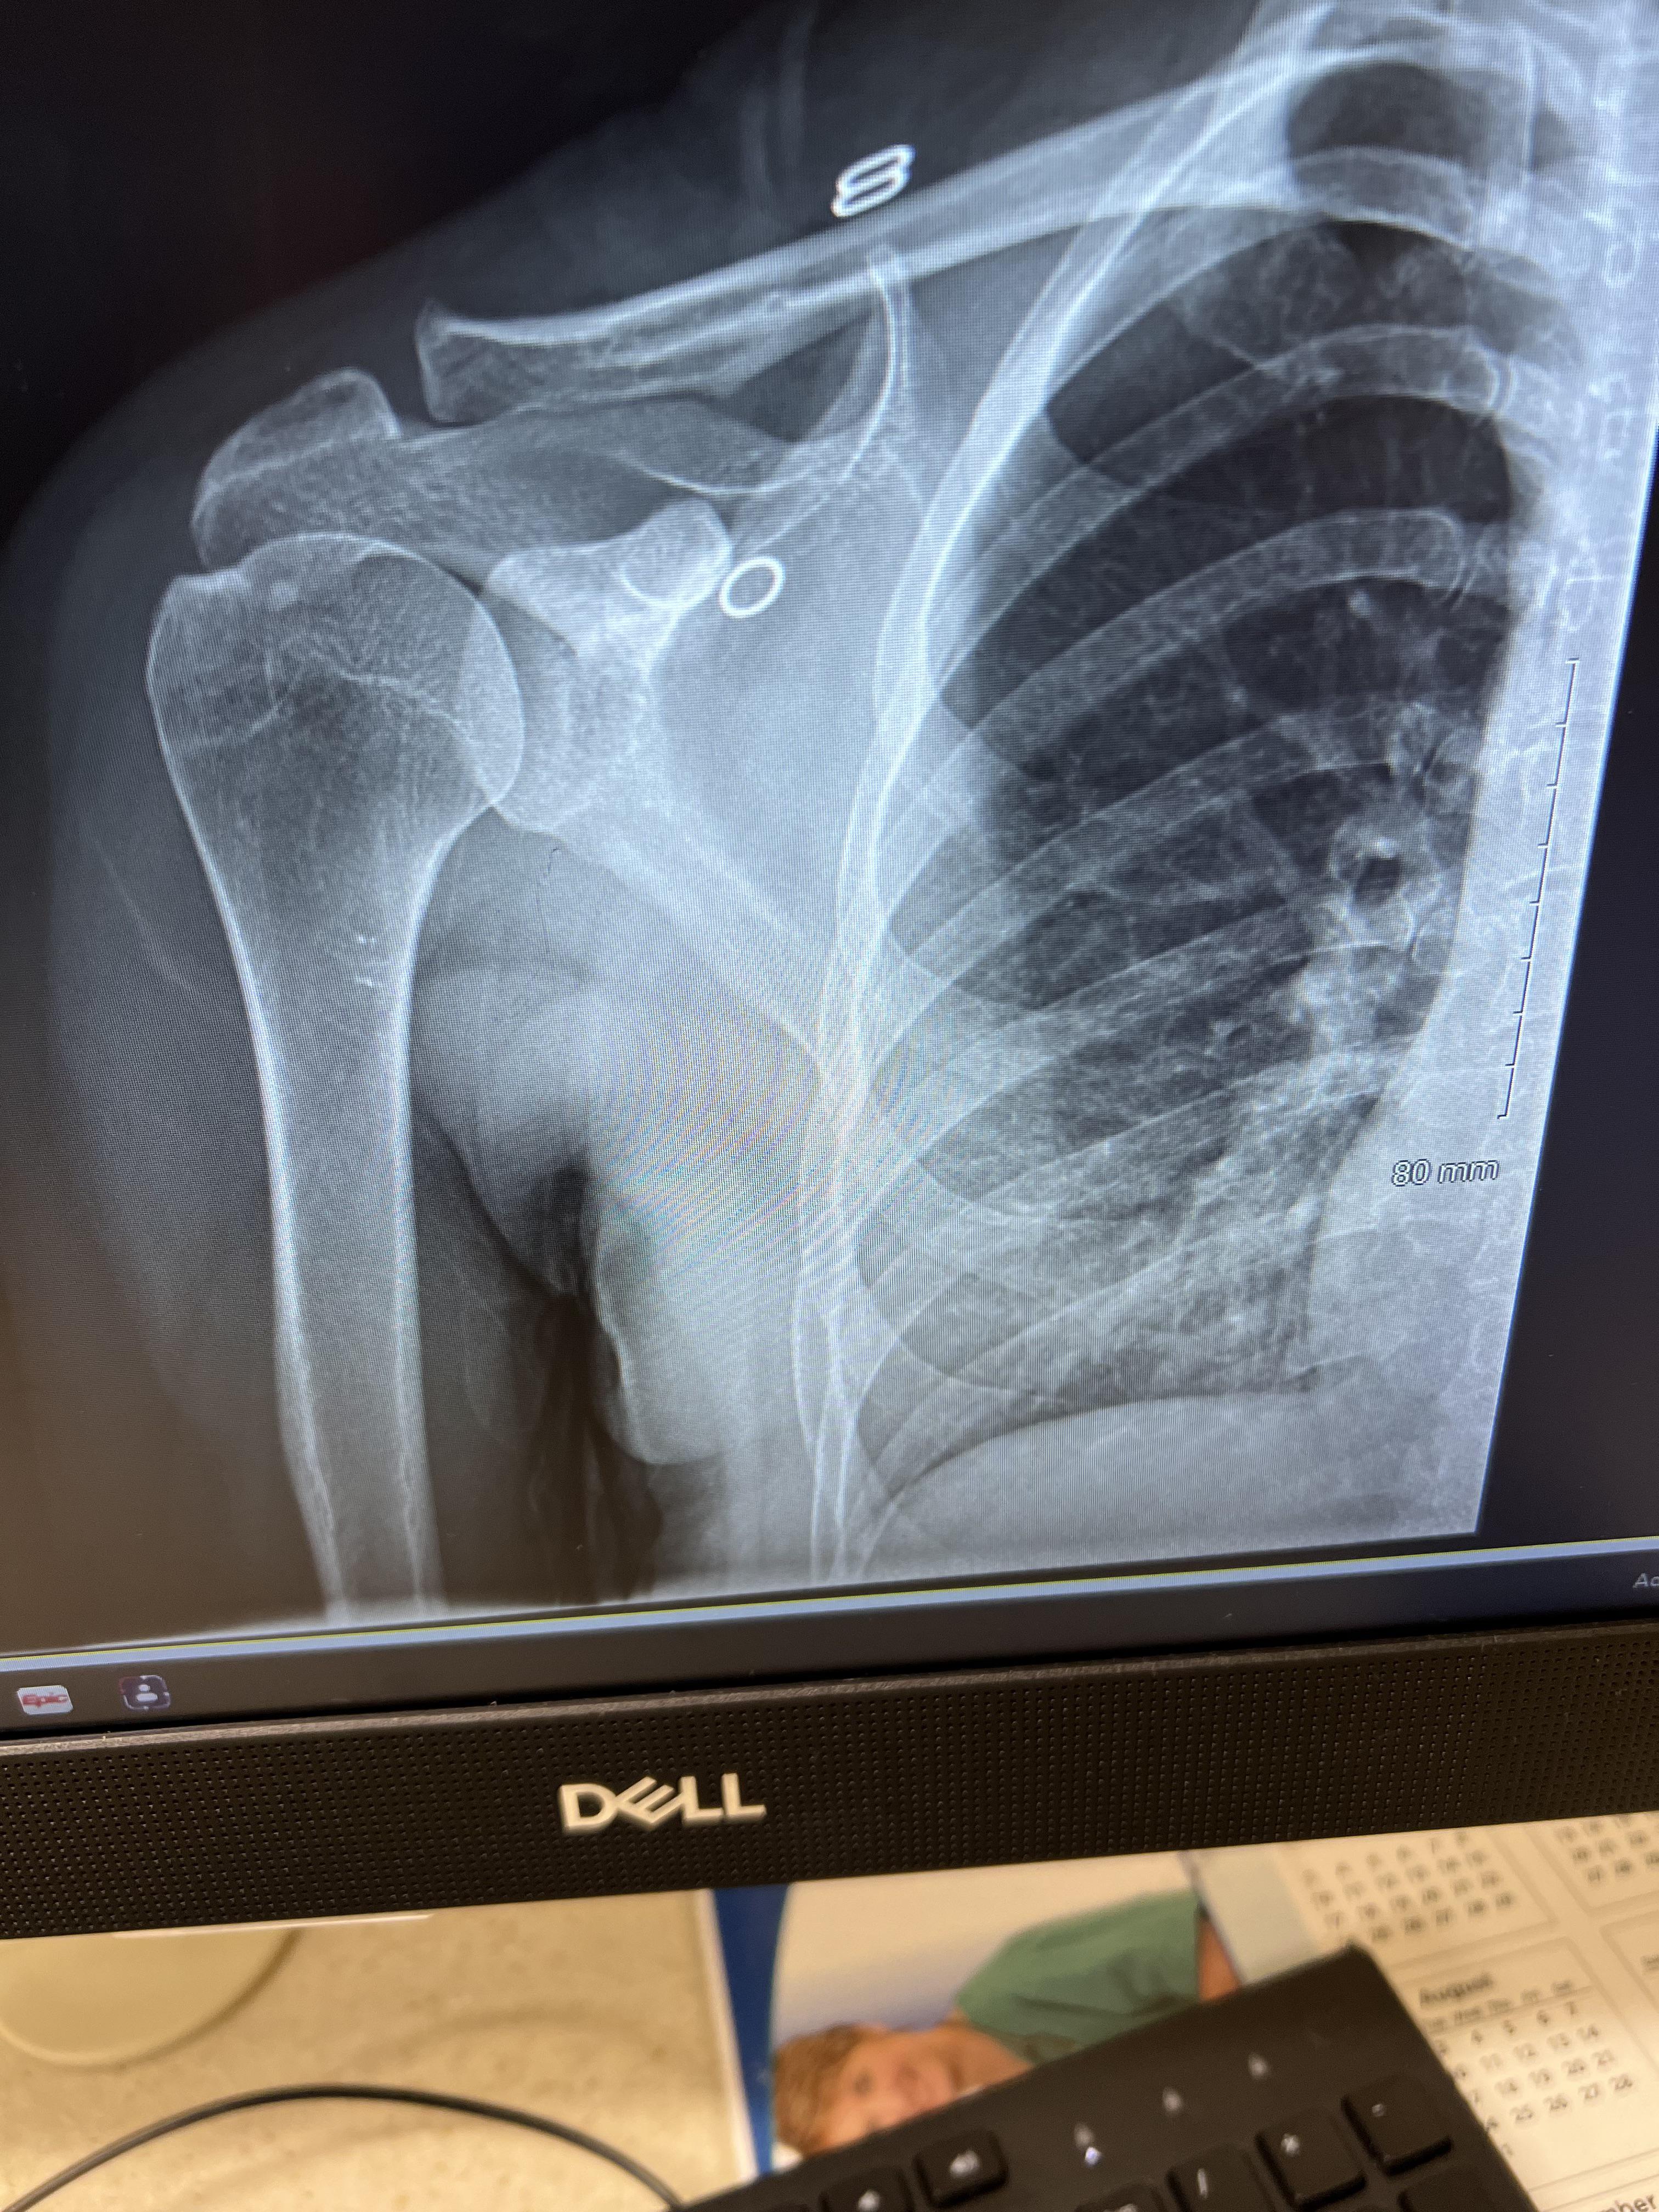

Clavicle Fractures Florida Orthopaedic Institute Pain In My Right Clavicle Area Collarbone or clavicle pain has many causes, from injuries to underlying health conditions. Collarbone pain can be related to trauma, poor sleeping positions, infections, and possible rare illnesses. Read below for more information on causes and how to treat pain in the collarbone and shoulder. Other common causes of clavicle pain include a frozen shoulder, rotator cuff tendonitis, or even. Pain In My Right Clavicle Area.

Clavicle Fracture (Broken Collarbone) OrthoInfo AAOS Pain In My Right Clavicle Area Collarbone pain can be caused by a fracture, arthritis, a bone infection, or another condition related to the position of your clavicle. Collarbone or clavicle pain has many causes, from injuries to underlying health conditions. The clavicle bone itself may be broken or suffering from wear and tear, the surrounding ligaments injured or occasionally. Severe or ongoing pain should be. Pain In My Right Clavicle Area.